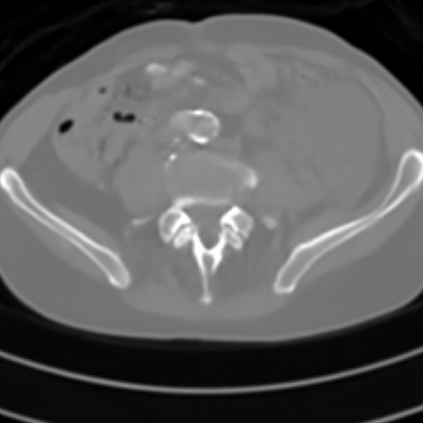

Sparse-view computed tomography (CT) -- using a small number of projections for tomographic reconstruction -- enables much lower radiation dose to patients and accelerated data acquisition. The reconstructed images, however, suffer from strong artifacts, greatly limiting their diagnostic value. Current trends for sparse-view CT turn to the raw data for better information recovery. The resultant dual-domain methods, nonetheless, suffer from secondary artifacts, especially in ultra-sparse view scenarios, and their generalization to other scanners/protocols is greatly limited. A crucial question arises: have the image post-processing methods reached the limit? Our answer is not yet. In this paper, we stick to image post-processing methods due to great flexibility and propose global representation (GloRe) distillation framework for sparse-view CT, termed GloReDi. First, we propose to learn GloRe with Fourier convolution, so each element in GloRe has an image-wide receptive field. Second, unlike methods that only use the full-view images for supervision, we propose to distill GloRe from intermediate-view reconstructed images that are readily available but not explored in previous literature. The success of GloRe distillation is attributed to two key components: representation directional distillation to align the GloRe directions, and band-pass-specific contrastive distillation to gain clinically important details. Extensive experiments demonstrate the superiority of the proposed GloReDi over the state-of-the-art methods, including dual-domain ones. The source code is available at https://github.com/longzilicart/GloReDi.